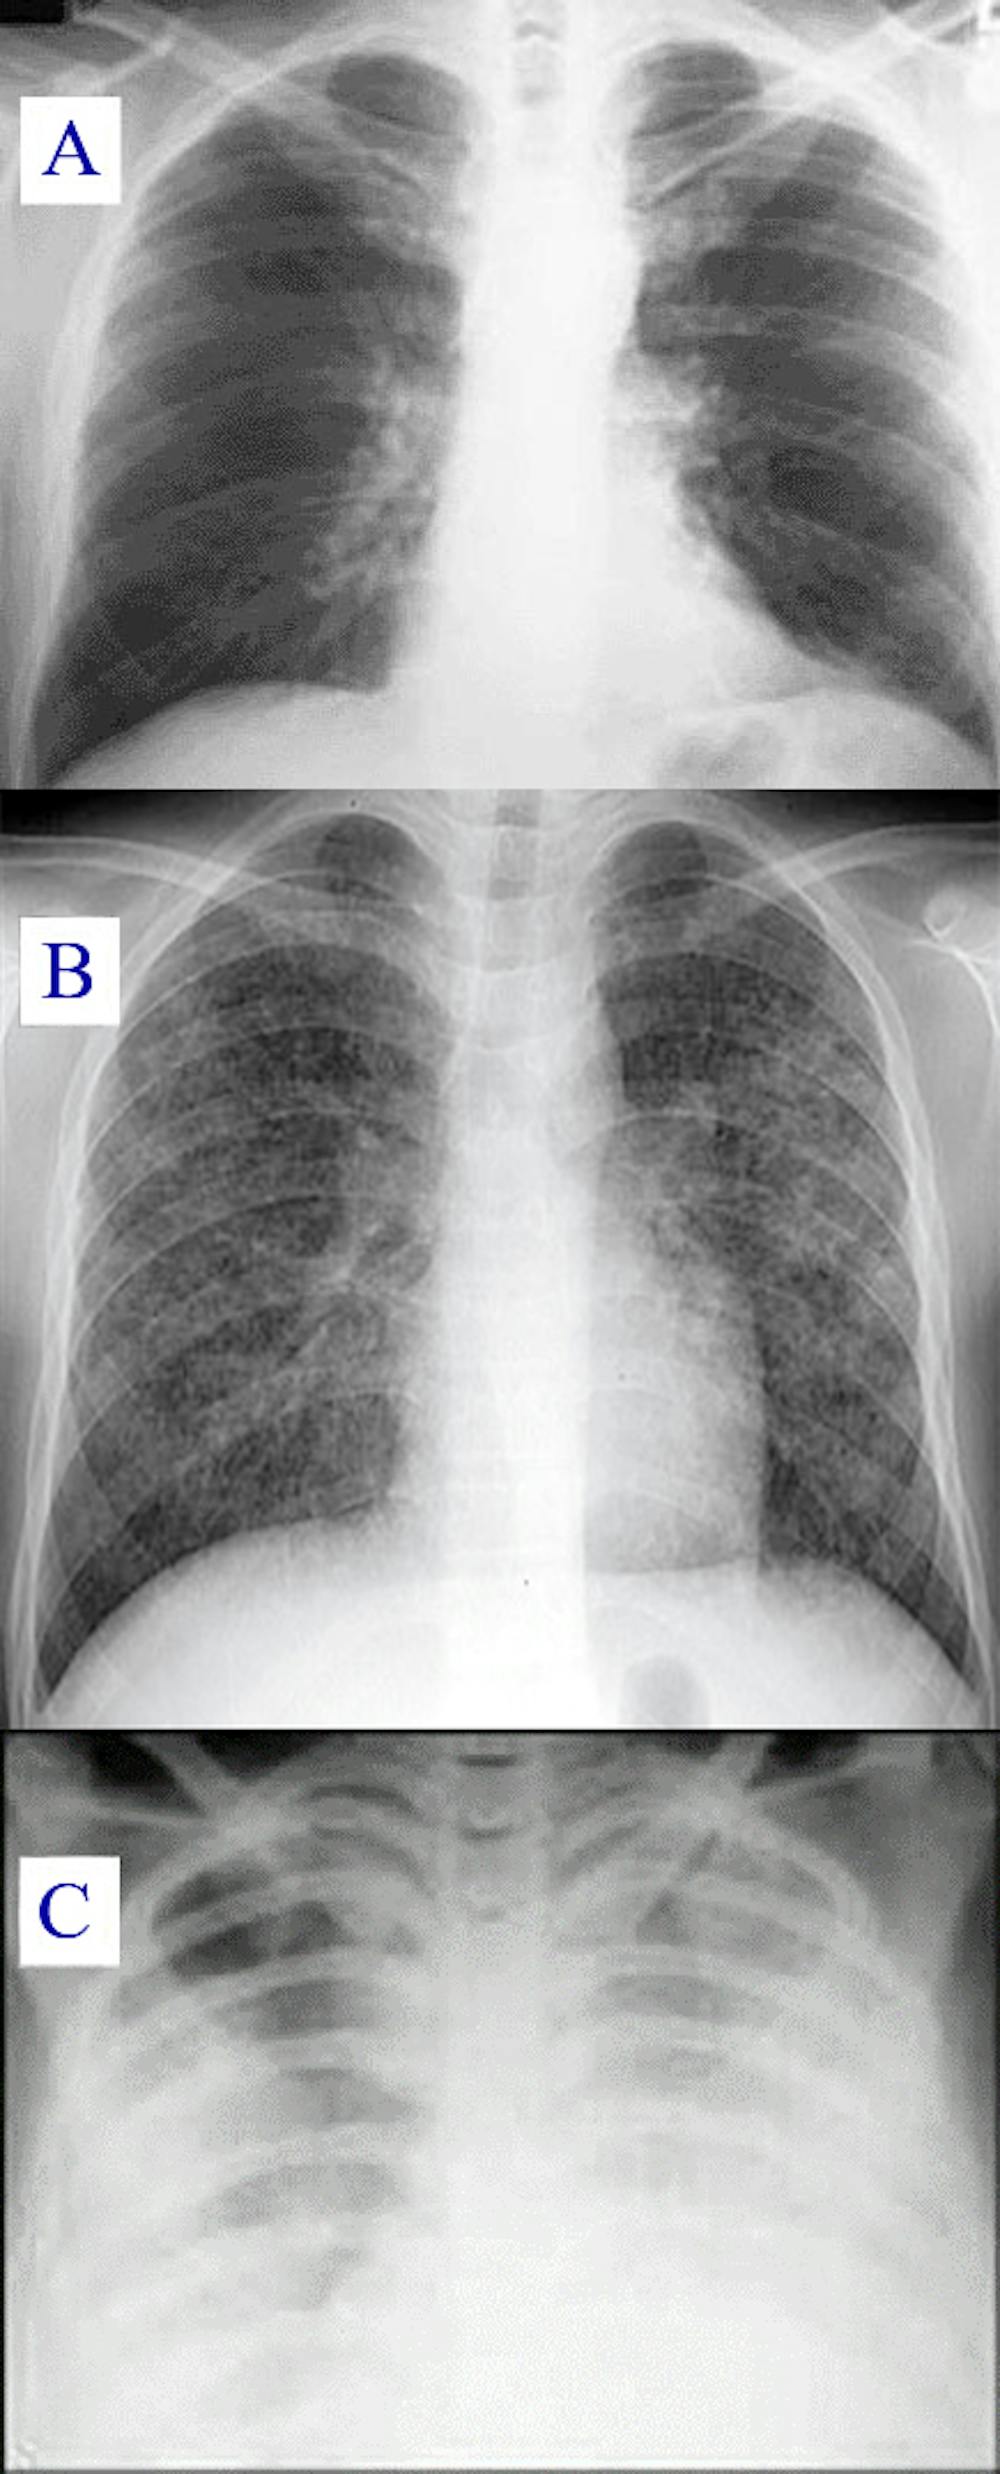

Dans leurs formes les plus graves, les pneumonies à SARS-CoV-2 sont responsables d’un tableau clinique appelé syndrome de détresse respiratoire aiguë (SDRA). Cette atteinte des deux poumons se traduit par une inflammation sévère qui entraîne la destruction des alvéoles pulmonaires, ainsi qu’un œdème important. Elle est associée à une mortalité allant de 30 à 50 % des patients.

La gravité potentielle d’une pneumonie réside dans le degré d’altération du fonctionnement pulmonaire. Celle-ci peut en effet entraîner un défaut d’apport en oxygène (hypoxémie), voire une détresse respiratoire, qui se traduit par une véritable « faillite » pulmonaire. L’hospitalisation est alors nécessaire.

Le scanner est devenu indispensable au diagnostic, car la radio seule s’est avérée très mauvaise pour quantifier la sévérité des COVID. Les radiologues ont mis au point des scores permettant de quantifier la gravité de l’atteinte (autrement dit, le pourcentage des zones atteintes) et le scanner permet de diagnostiquer une embolie pulmonaire associée. Les thromboses (caillot obstruant un vaisseau sanguin) sont en effet des complications fréquentes de la Covid-19.